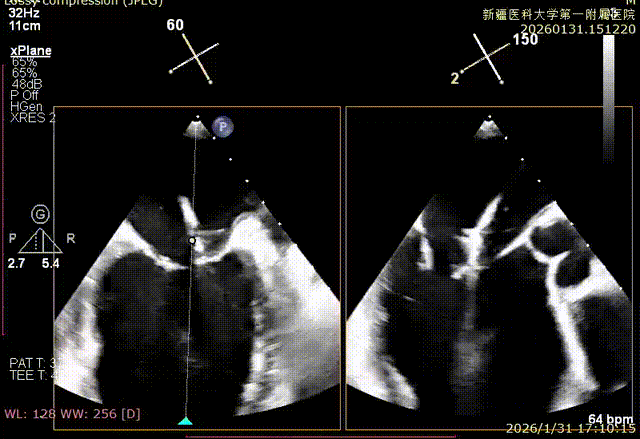

成功捕捞瓣叶并夹持

缓慢关紧夹臂

双孔组织桥稳定

术后平均跨瓣压差1mmHg

捕捞足够瓣叶后下Gripper,bouncing明显

缓慢关紧夹臂,同时小心多次释放张力